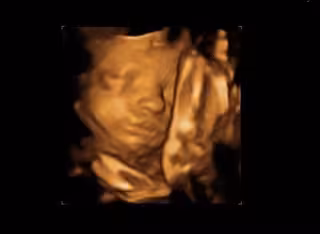

Consiguen la primera prueba directa de que los bebés reaccionan al gusto y al olor en el útero

Archivo - Ecografía

Un estudio dirigido por el Laboratorio de Investigación Fetal y Neonatal de la Universidad de Durham (Reino Unido) tomó ecografías en 4D de 100 mujeres embarazadas para ver cómo respondían sus bebés no nacidos tras ser expuestos a los sabores de los alimentos que comían sus madres. Los investigadores observaron cómo reaccionaban los fetos a los sabores de la zanahoria o la col rizada poco tiempo después de que las madres los hubieran ingerido, según publican en la revista 'Psychological Science'.

Los fetos expuestos a la zanahoria mostraron más respuestas de "cara de risa", mientras que los expuestos a la col rizada mostraron más respuestas de "cara de llanto". Estos resultados, aseguran los autores, podrían ayudar a comprender mejor el desarrollo de los receptores del gusto y el olfato en el ser humano.